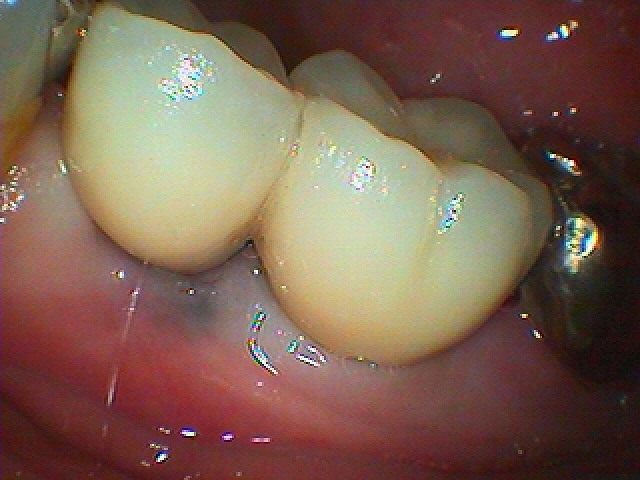

6番部の支台歯を見ていきます

中は土台も入っていません

歯に穴が開いていて分岐部の骨吸収も生じていました